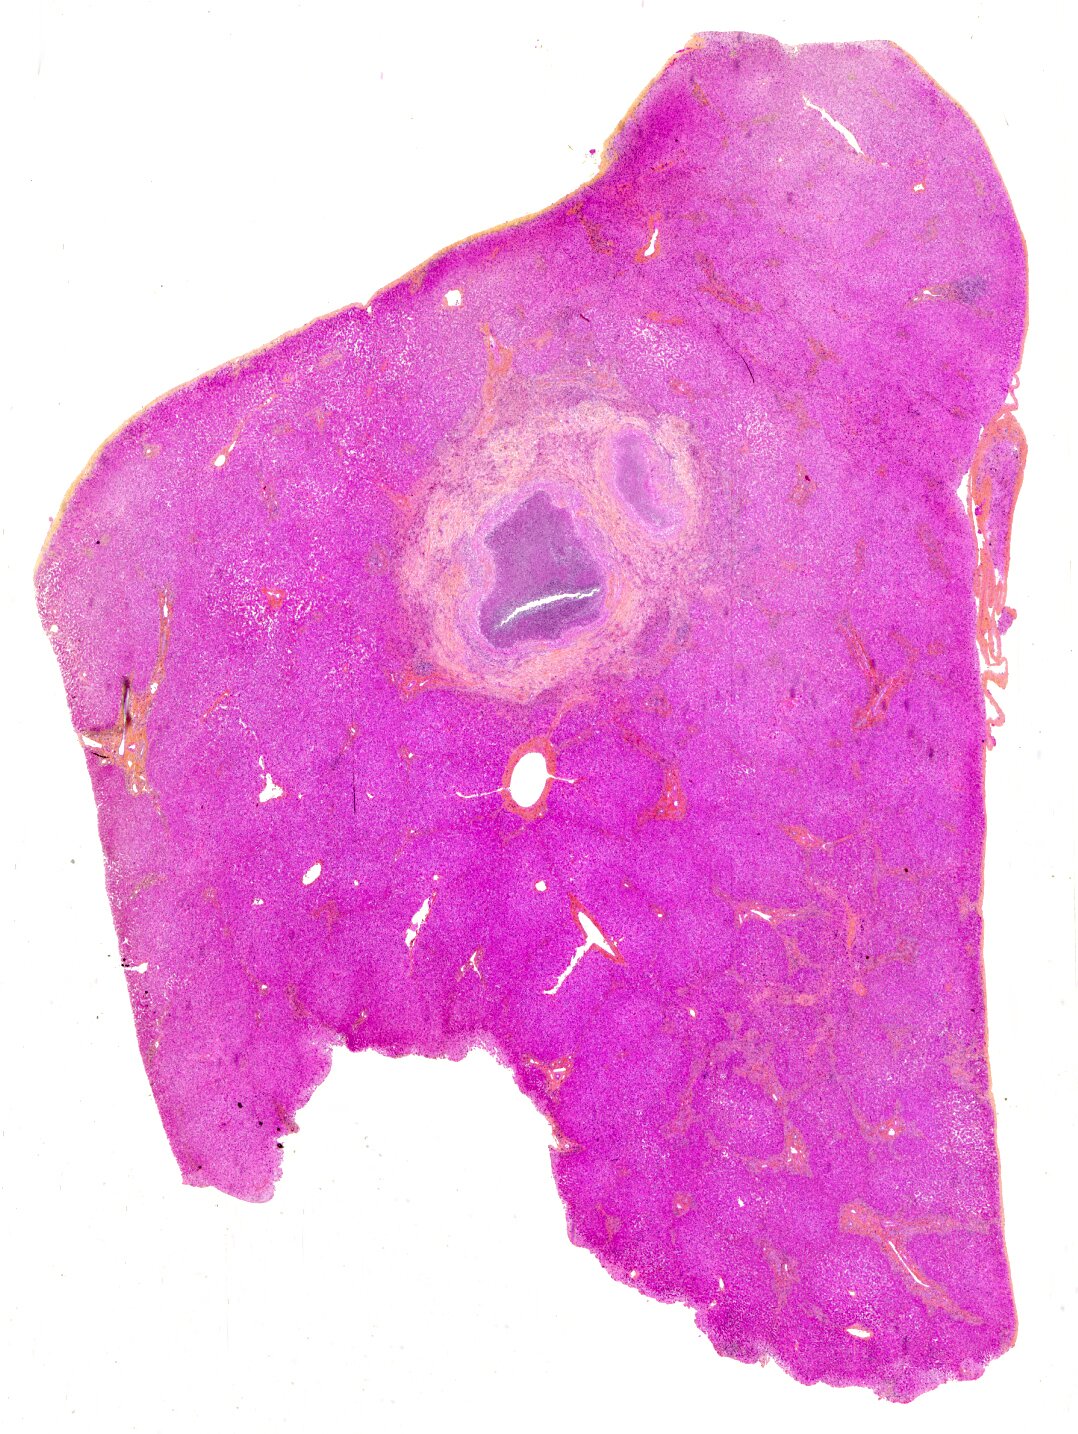

necrotizing granuloma